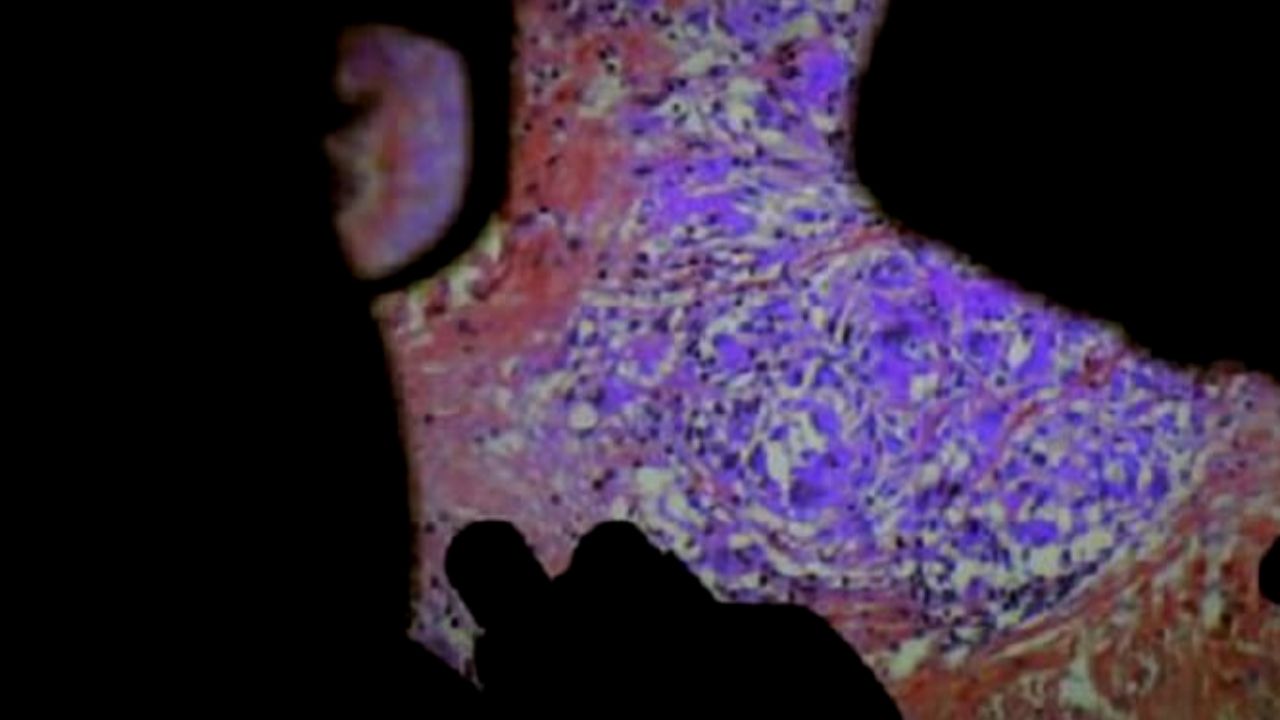

A través de cámaras endoscópicas, la película nos muestra órganos internos, procedimientos quirúrgicos y momentos íntimos entre médicos y pacientes. Desde una cesárea hasta la inserción de un catéter, De Humani Corporis Fabrica revela tanto la belleza, como la sorpresa y la incomodidad de estos encuentros con el interior de nuestros cuerpos.

A lo largo de la producción, incluso los propios cirujanos se ven desafiados por la complejidad del cuerpo humano, lo que lleva a momentos de reflexión y asombro.